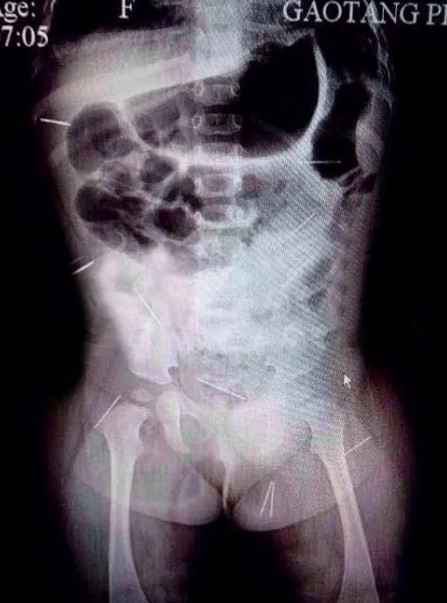

Kết quả chụp X-quang cho thấy cơ thể bé gái có 12 mũi kim khâu, rõ ràng có ai đó đã cố tình dùng kim đâm vào người bé. Anh Fan Guangsheng, cha ruột của bé cho biết trước đó một tháng, các bác sĩ cũng phát hiện cháu có 4 cây kim trong cơ thể, nhưng lúc đó anh và vợ cho rằng con gặp tai nạn nên không đề nghị điều tra.

Trong số 12 mũi kim được lấy ra từ cơ thể Fan Zixuan, 10 mũi là kim tiêm dưới da, hai mũi còn lại là kim khâu, theo các bác sĩ.